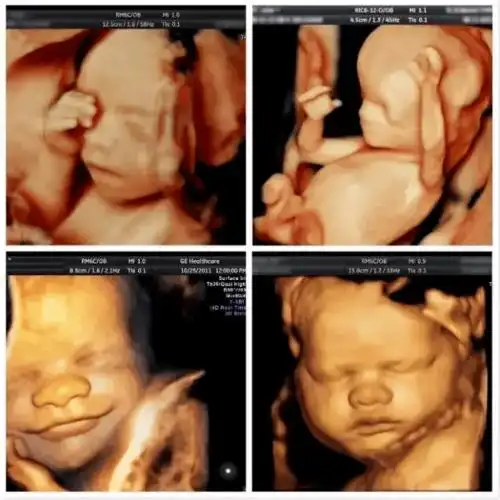

之前陪表妹去产检的,当时也选的四维彩超,想要留张胎儿的照片做纪念.